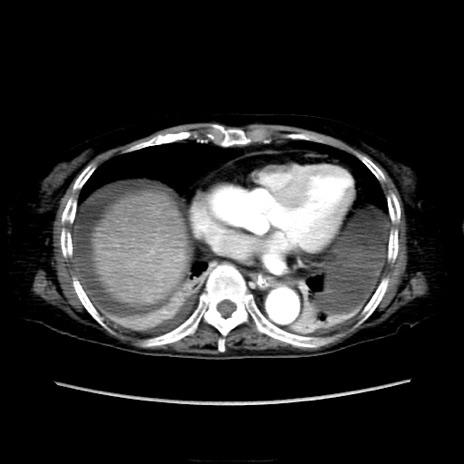

冠状断像

症例40(横断像)

【症例】90歳代女性

【主訴】腹痛・嘔吐

【身体所見】腹部:中央に激痛あり、圧痛あり、反跳痛不明

【データ】WBC 17100、CRP 18.82